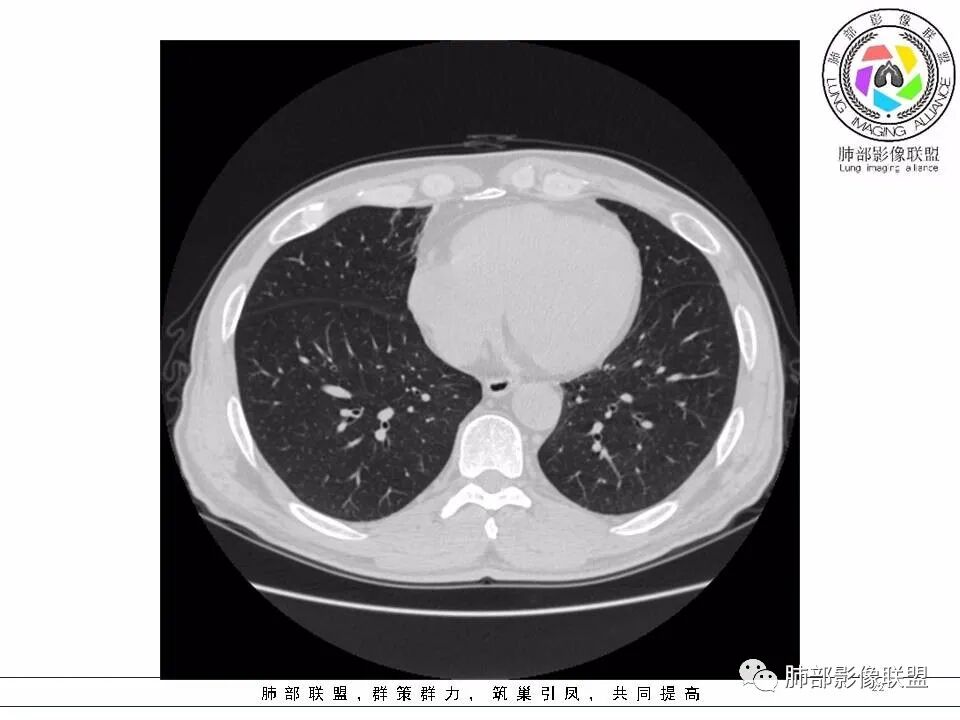

2.左肺下叶外基底段囊腔样病灶,轮廓柔和,壁厚薄不均,见壁结节。内见分隔或脊状突起。腔内见血管穿行。

这是有“故事”的囊!

3.囊壁外环以磨玻璃影,边界较清楚。

1.囊腔壁厚薄不均,壁结节,内有分隔,其内有血管穿行,指向新生物。

2.临近有边界清楚磨玻璃影,指向腺癌。